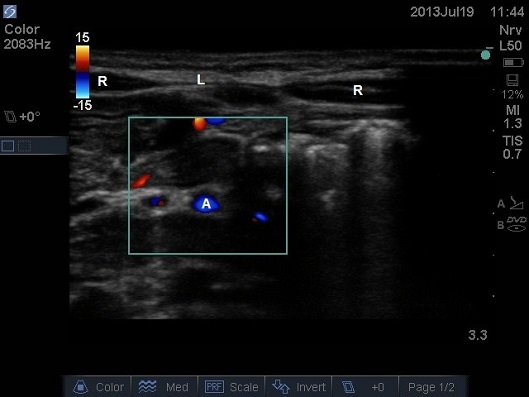

ULTRASOUND OF NEONATAL ABDOMEN IN TRANSVERSE PLANE. A – AORTA, L – LINEA ALBA, R – RECTUS MUSCLE

- Select highest appropriate frequency for the initial scanning depth.

- The initial image will have the linea alba in the midline with a rectus abdominis muscle either side.

- In larger children it is possible to identify the epigastric vessels with Doppler. Ensure the probe pressure is minimal.